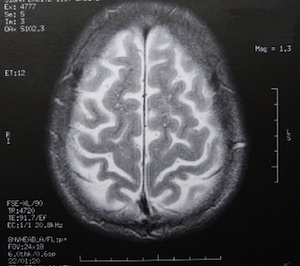

Sie sind hier: Startseite Nachrichten Gesundheit Wissenschaftler entdecken rätselhafte Tunnel im Menschenhirn Bild: pixelio.de/Dieter Schütz

Bild: pixelio.de/Dieter Schütz